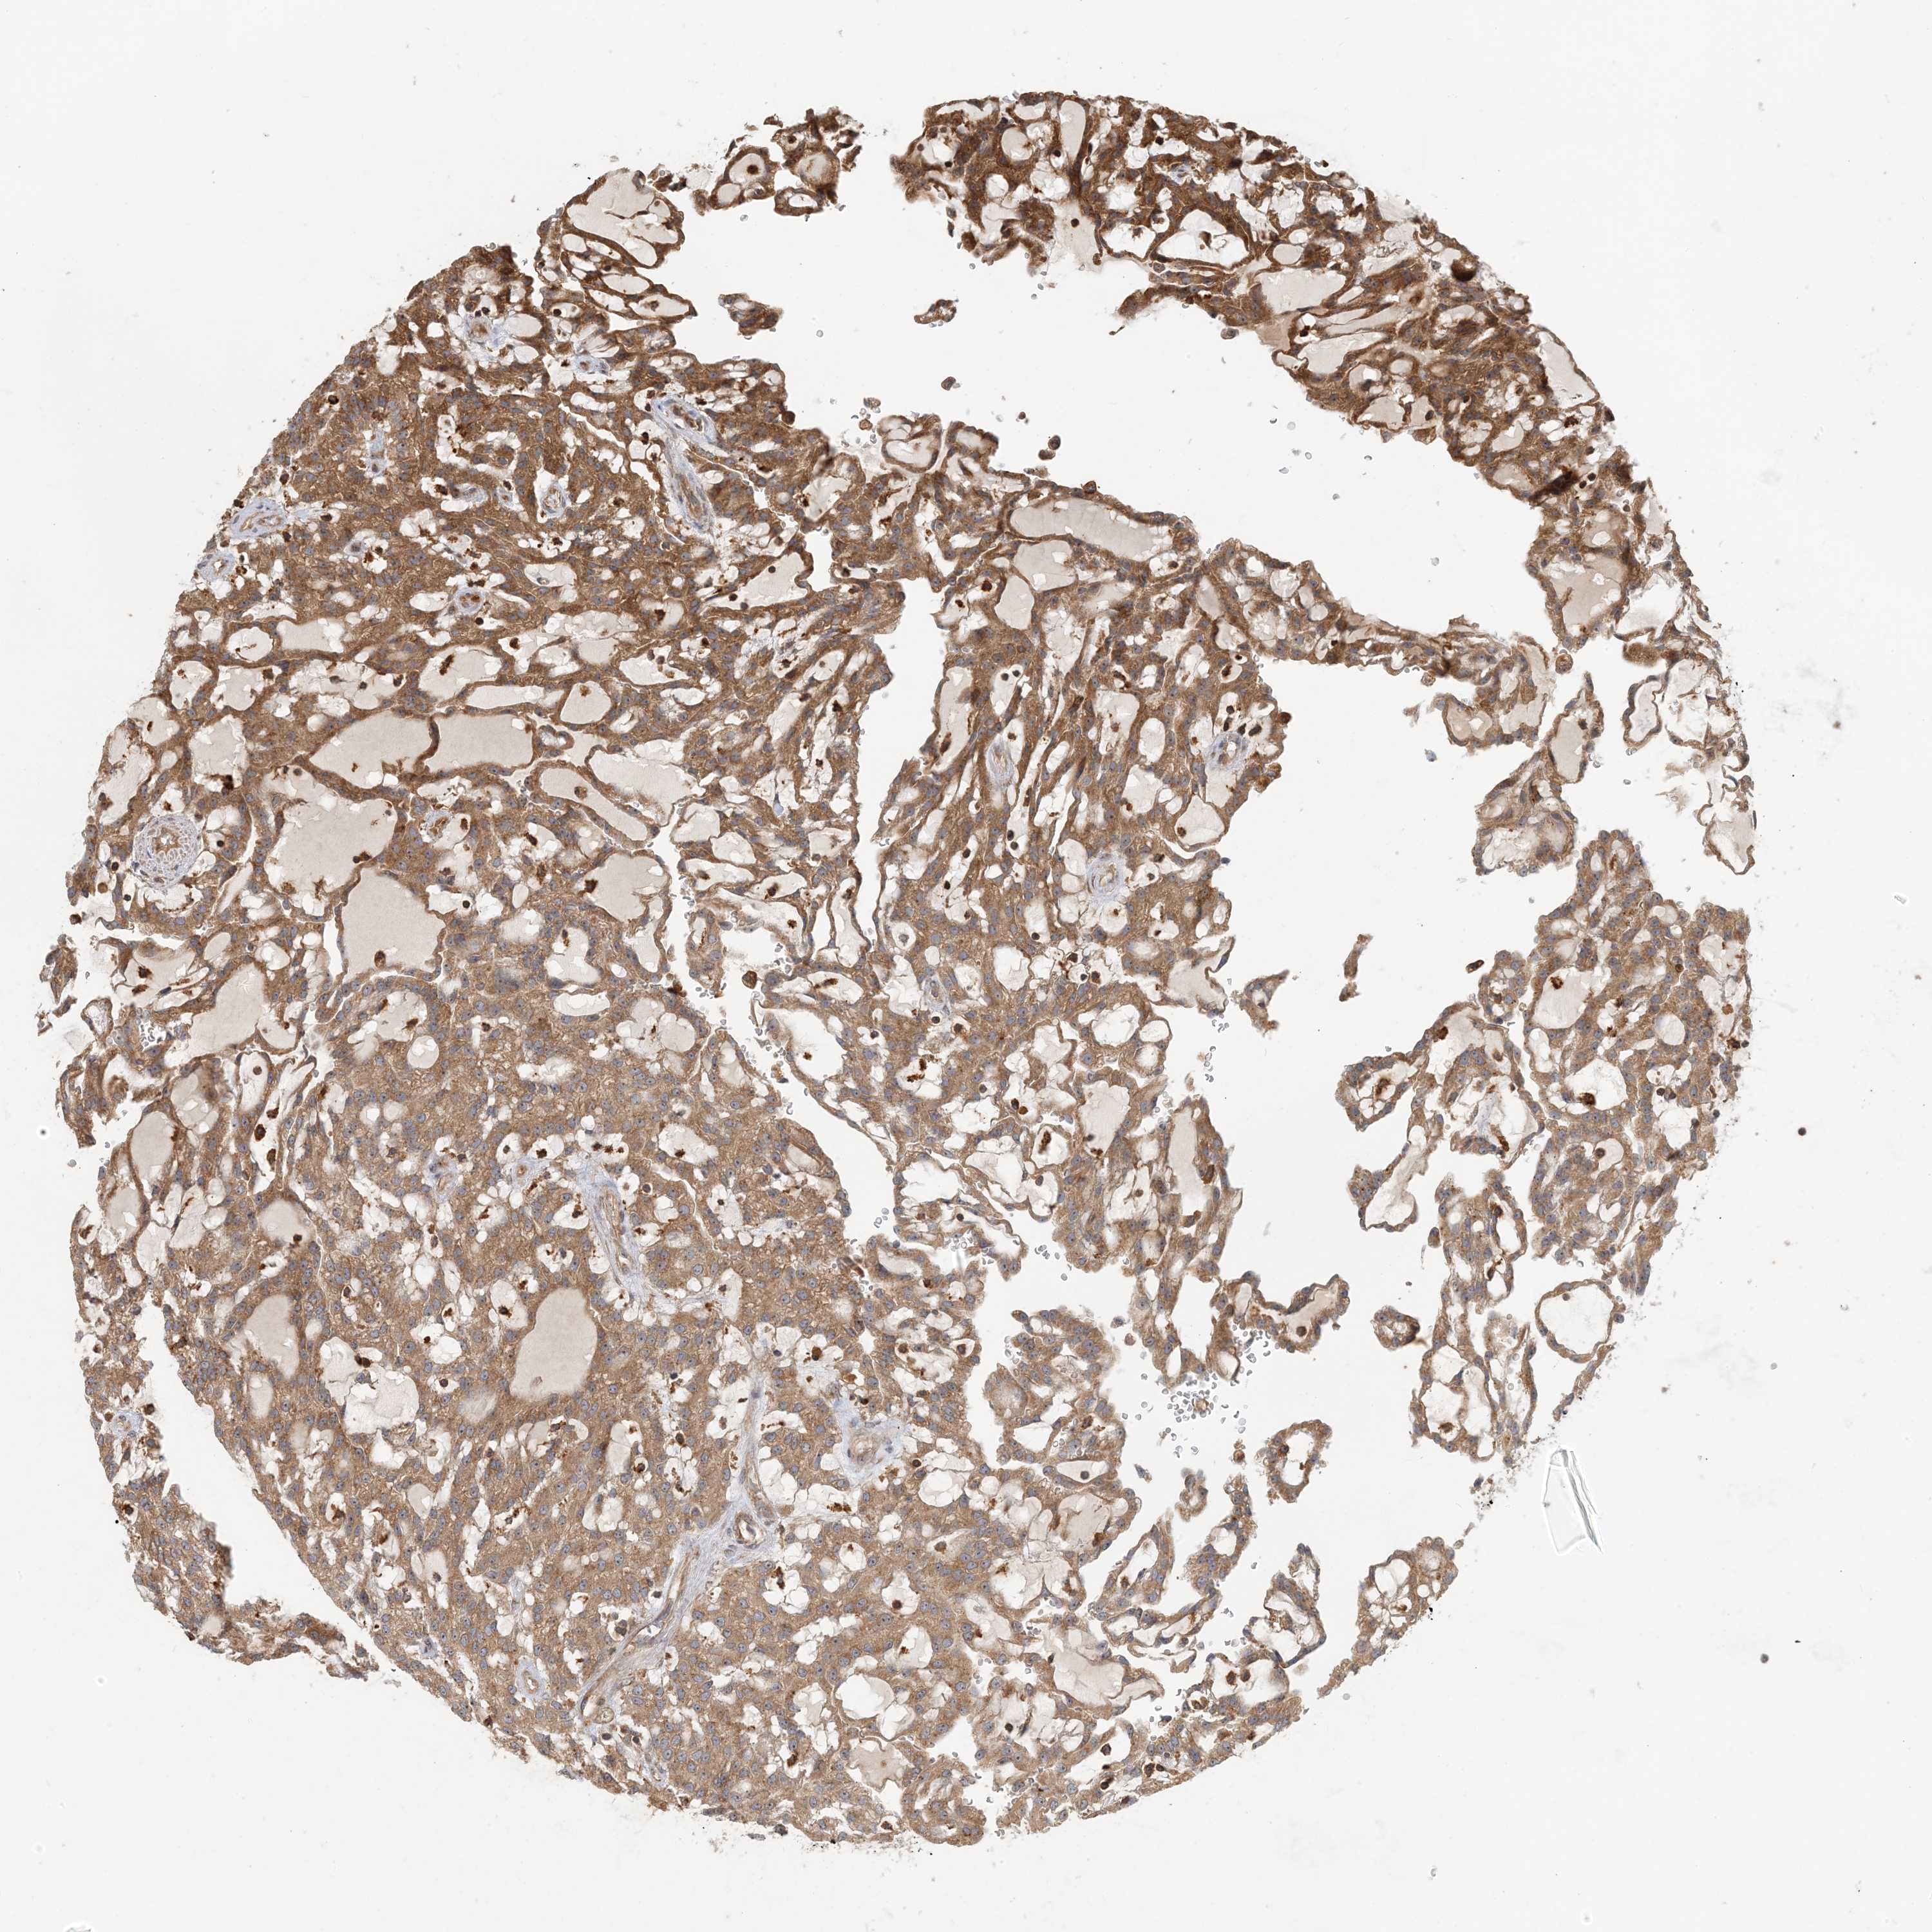

Average pTPM 10.1

Number of samples 521